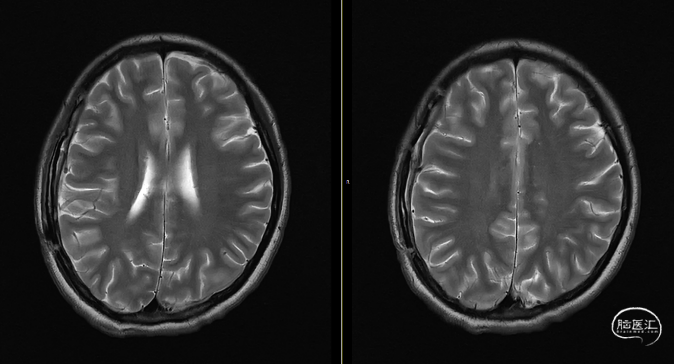

第3次术后23天,拔管后7天复查颅脑(如上图)。

第3次手术后49天,出院后2周复查颅脑CT情况(如上图),刀口愈合正常,患者回归日常生活、学习。